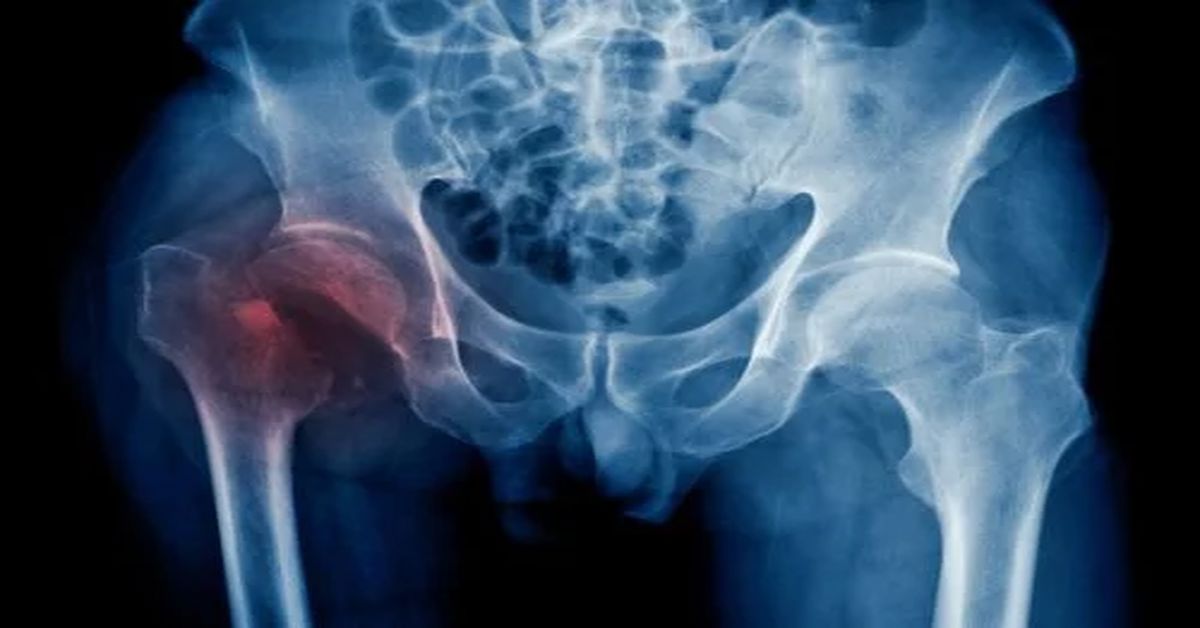

Kalça bölgesinde meydana gelen kırıkların cerrahi olarak tedavi edilmesidir. Kalça kırığı ameliyatı genellikle travma sonrası ya da osteoporoz gibi nedenlerle oluşan kalça kırıklarında uygulanır. Ameliyat, kırığın türüne ve yerine bağlı olarak değişiklik gösterebilir. Kırığın düzeltilmesi ve kalçanın fonksiyonlarının yeniden sağlanması amaçlanır. İyileşme süreci, cerrahi teknik ve hastanın genel sağlık durumuna bağlı olarak değişiklik gösterebilir.

Kalça kırıkları genellikle düşme veya trafik kazası gibi travmalar sonucunda ortaya çıkar. Bu durum ortopedik bir yaralanma olarak değerlendirilir. Özellikle ileri yaş grubunda görülen kalça kırıkları kişinin hareket kabiliyetini önemli ölçüde etkileyebilir.

İleri yaş grubundaki kişiler kalça kırıkları açısından daha fazla risk taşıyabilir. Bunun en önemli nedenlerinden biri kemik yoğunluğunun azalmasıdır. Osteoporoz gibi hastalıklar kemiklerin daha kırılgan hale gelmesine yol açabilir. Bu nedenle basit bir düşme bile kalça kırığına neden olabilir. Bunun yanında trafik kazaları veya yüksek enerjili travmalar genç bireylerde de kalça kırıklarının görülmesine yol açabilir. Kırığın şekli ve hastanın genel sağlık durumu tedavi yönteminin belirlenmesinde önemli rol oynar.